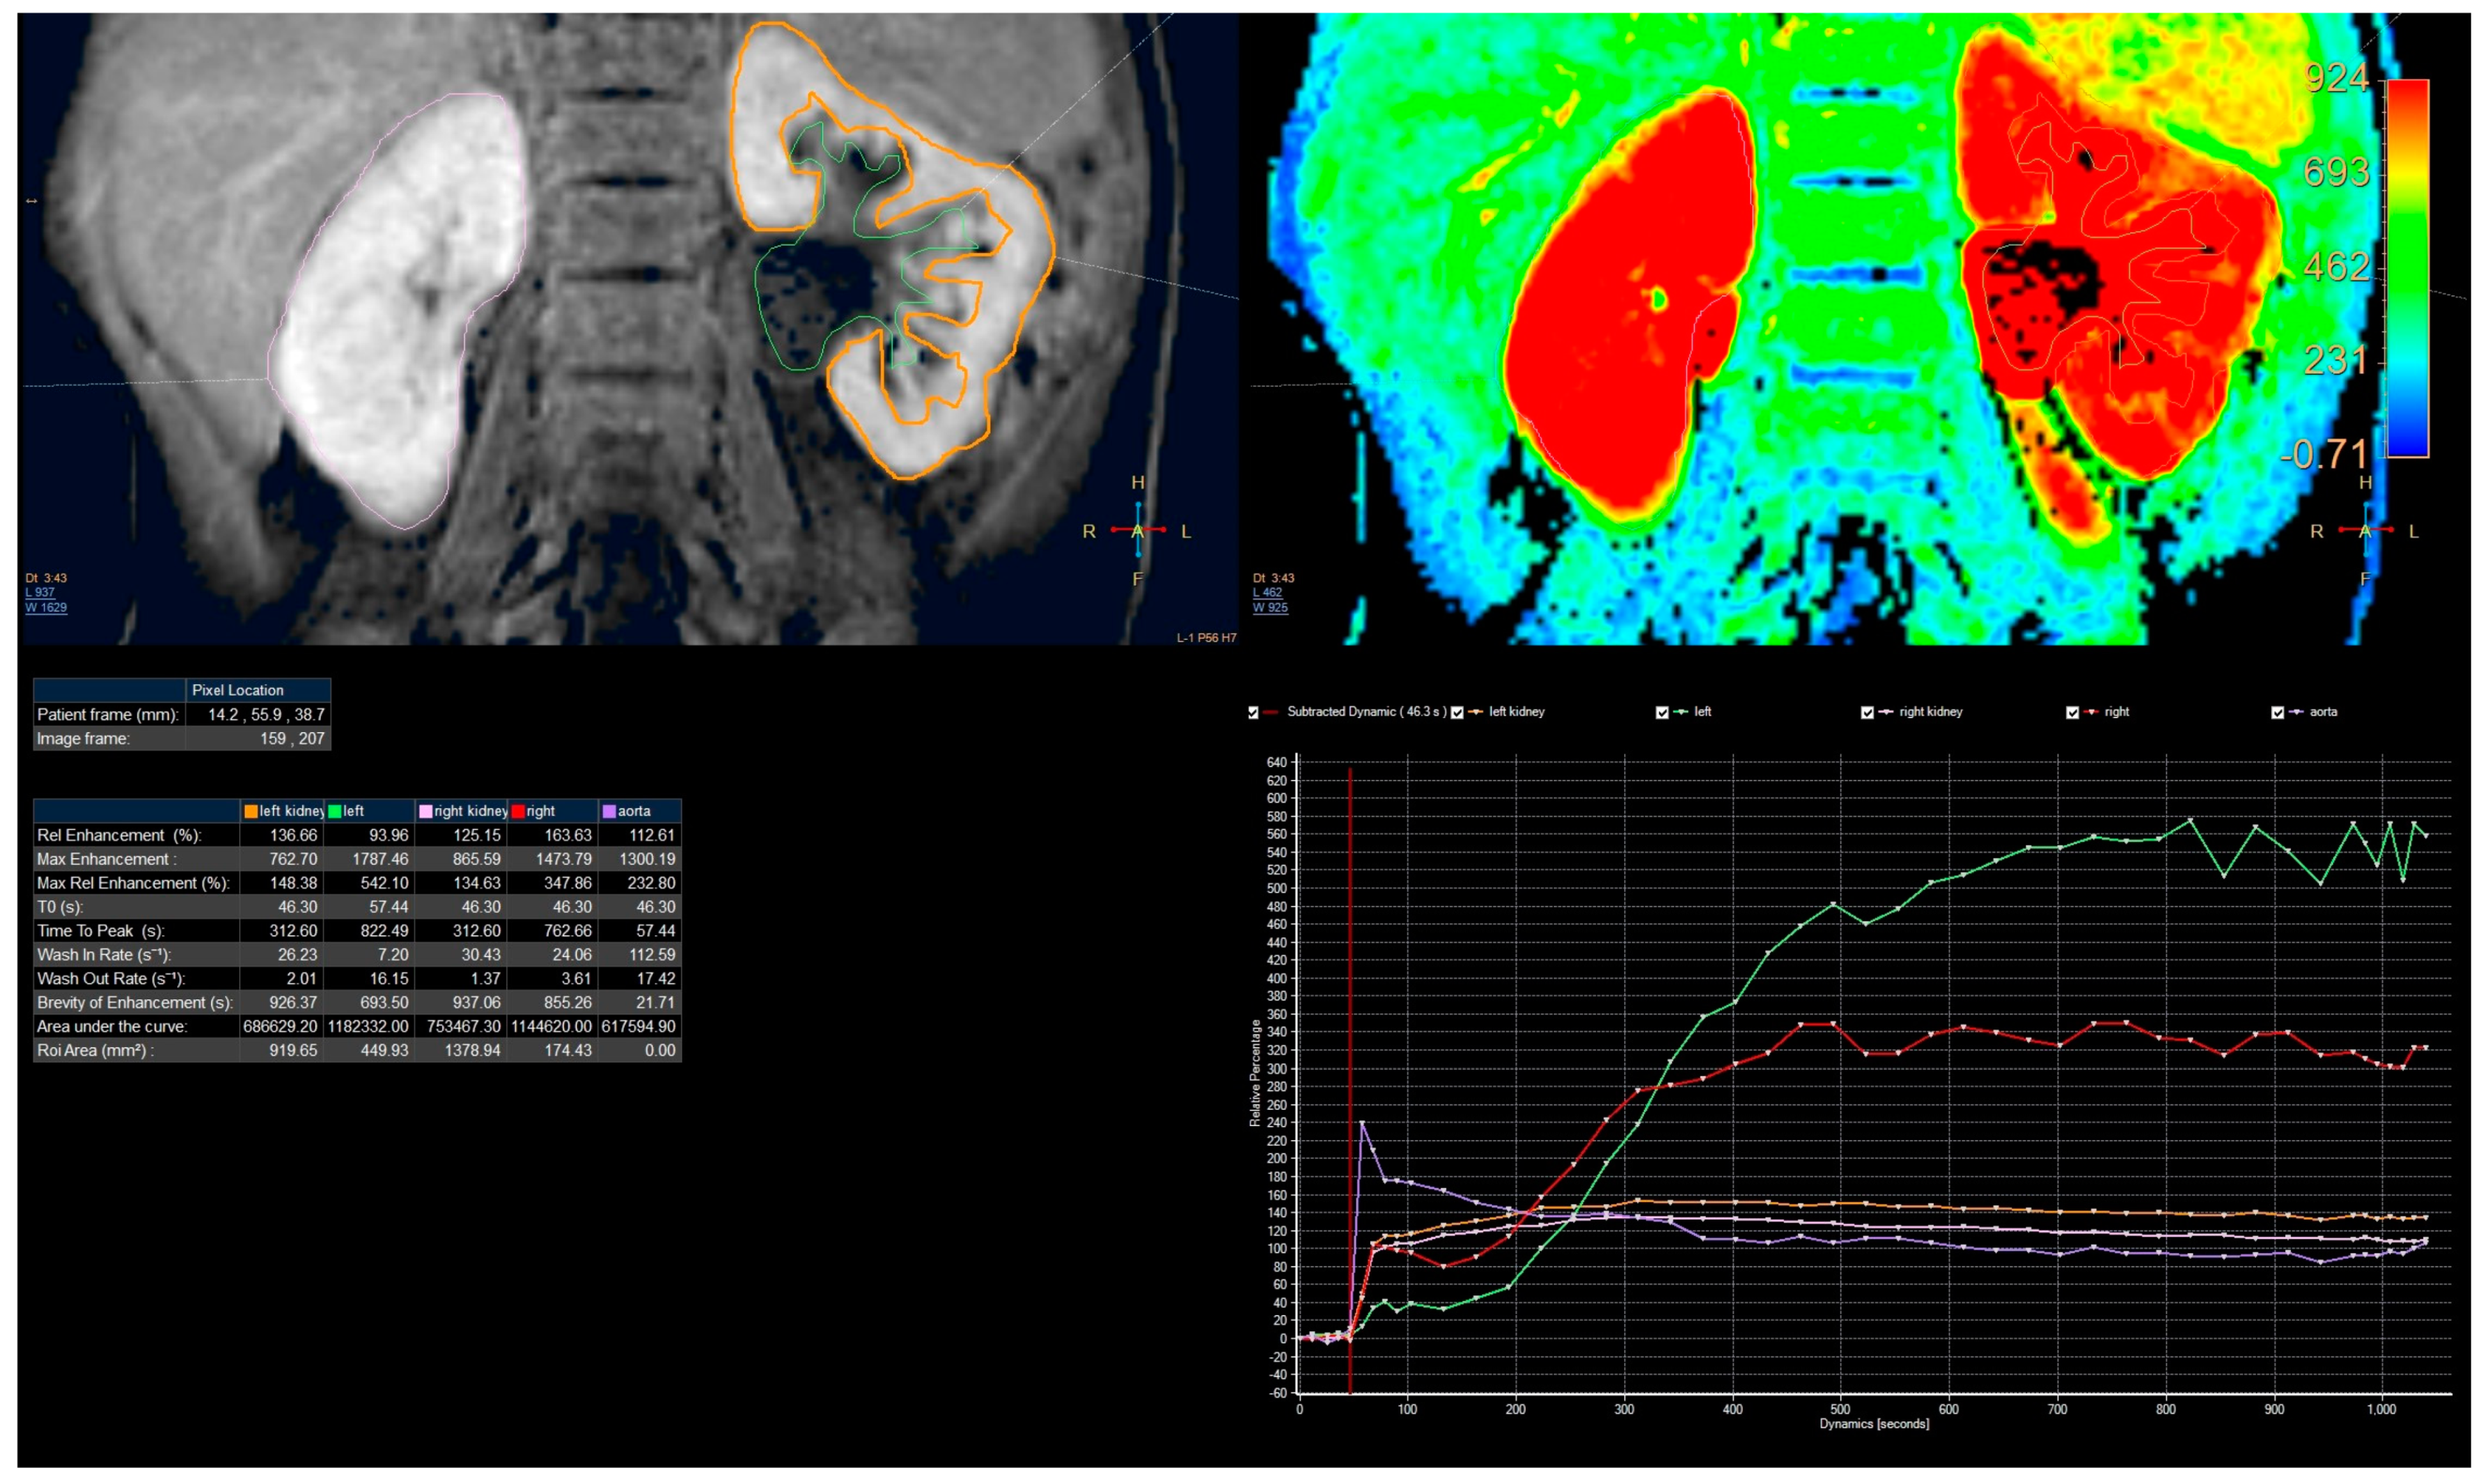

- Biophysical model analysis (Figure 5)—estimation of functional parameters for the aorta and each kidney.